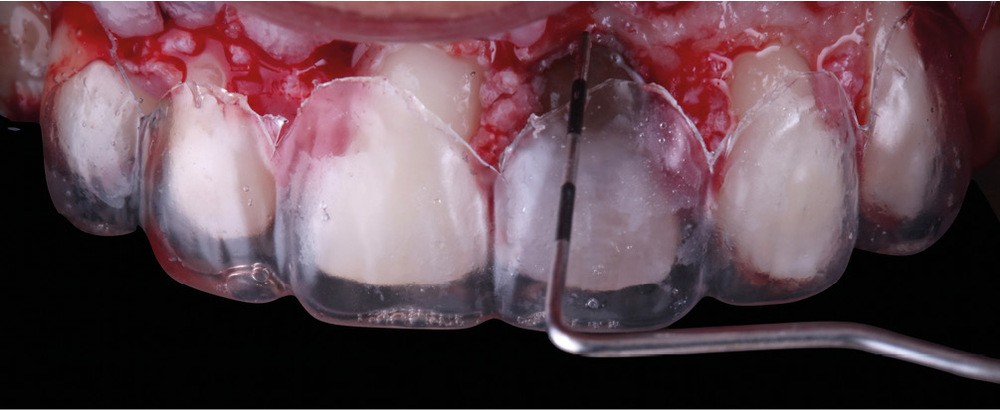

Acte 3 : gestion du rose soustractive (fig. 3 et 4)

Le laboratoire réalise d’abord un montage en cire (wax-up) à partir duquel une gouttière thermoformée sera préparée au cabinet. L’emplacement des futures dents, et surtout des futurs collets, est objectivé et nous guidera pour notre élongation coronaire. Cette chirurgie correctrice soustractive débute par une gingivectomie. Les collets une fois alignés, nous réalisons une ostéotomie/ostéoplastie. L’os vestibulaire est resséqué et positionné à 3 mm des futurs collets.